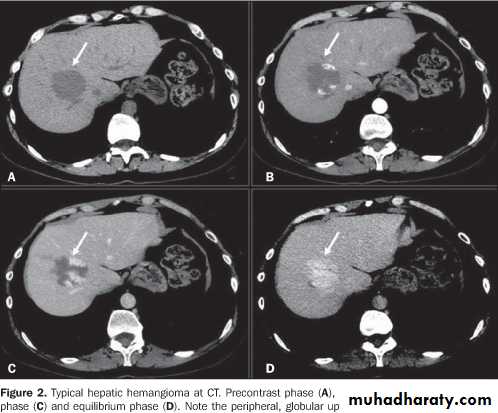

Hemangioma